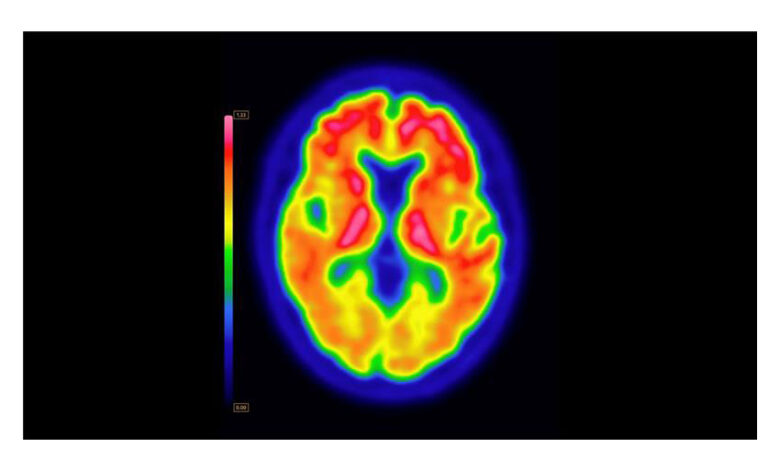

ARLINGTON HEIGHTS, Ill.–(BUSINESS WIRE)–GE HealthCare (Nasdaq: GEHC) today announced that the U.S. Food and Drug Administration (FDA) has approved an updated label for its positron emission tomography (PET) imaging agent VizamylTM (flutemetamol F 18 injection) for beta-amyloid detection. The revised label, effective immediately, expands the indications for use, enables quantitative analysis of Vizamyl scans, and removes significant previous limitations such as monitoring patient response to anti-amyloid therapy.

Up to now, amyloid diagnostics such as Vizamyl have been used to provide a visual assessment of amyloid plaque accumulation in the brain. With quantification now added to the label, clinicians can reach a more objective assessment, using software that enables a calculation of amyloid load, with published research demonstrating that quantification improves diagnostic confidence and consistency among readers1,2,3. In addition, with the removal of a limitation of use for monitoring therapy effectiveness, Vizamyl can also now be used to assess whether the level of amyloid plaques has been reduced sufficiently for the therapy to potentially be stopped.